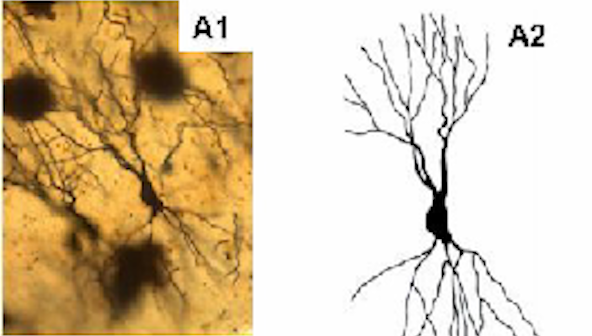

Another study also showed that acetylcholine increases dendrites

Dendrites are like signal receivers

The more dendrites you have, the better you can store and retrieve information, process information and make decisions

Look at the image below…

Pay attention to the branches (dendrites)

This is what happens when you are low on acetylcholine

Now, look at the image below again…

Pay attention to the branches also… you can see they are a lot compared to the first image above

The more of these branches you have, the better your memory will be

This is what the sacred memory and brain heal-all herb has been able to do

And it will do the same thing to your memory and brain

It will massively increase your acetylcholine which means better memory and better brain power